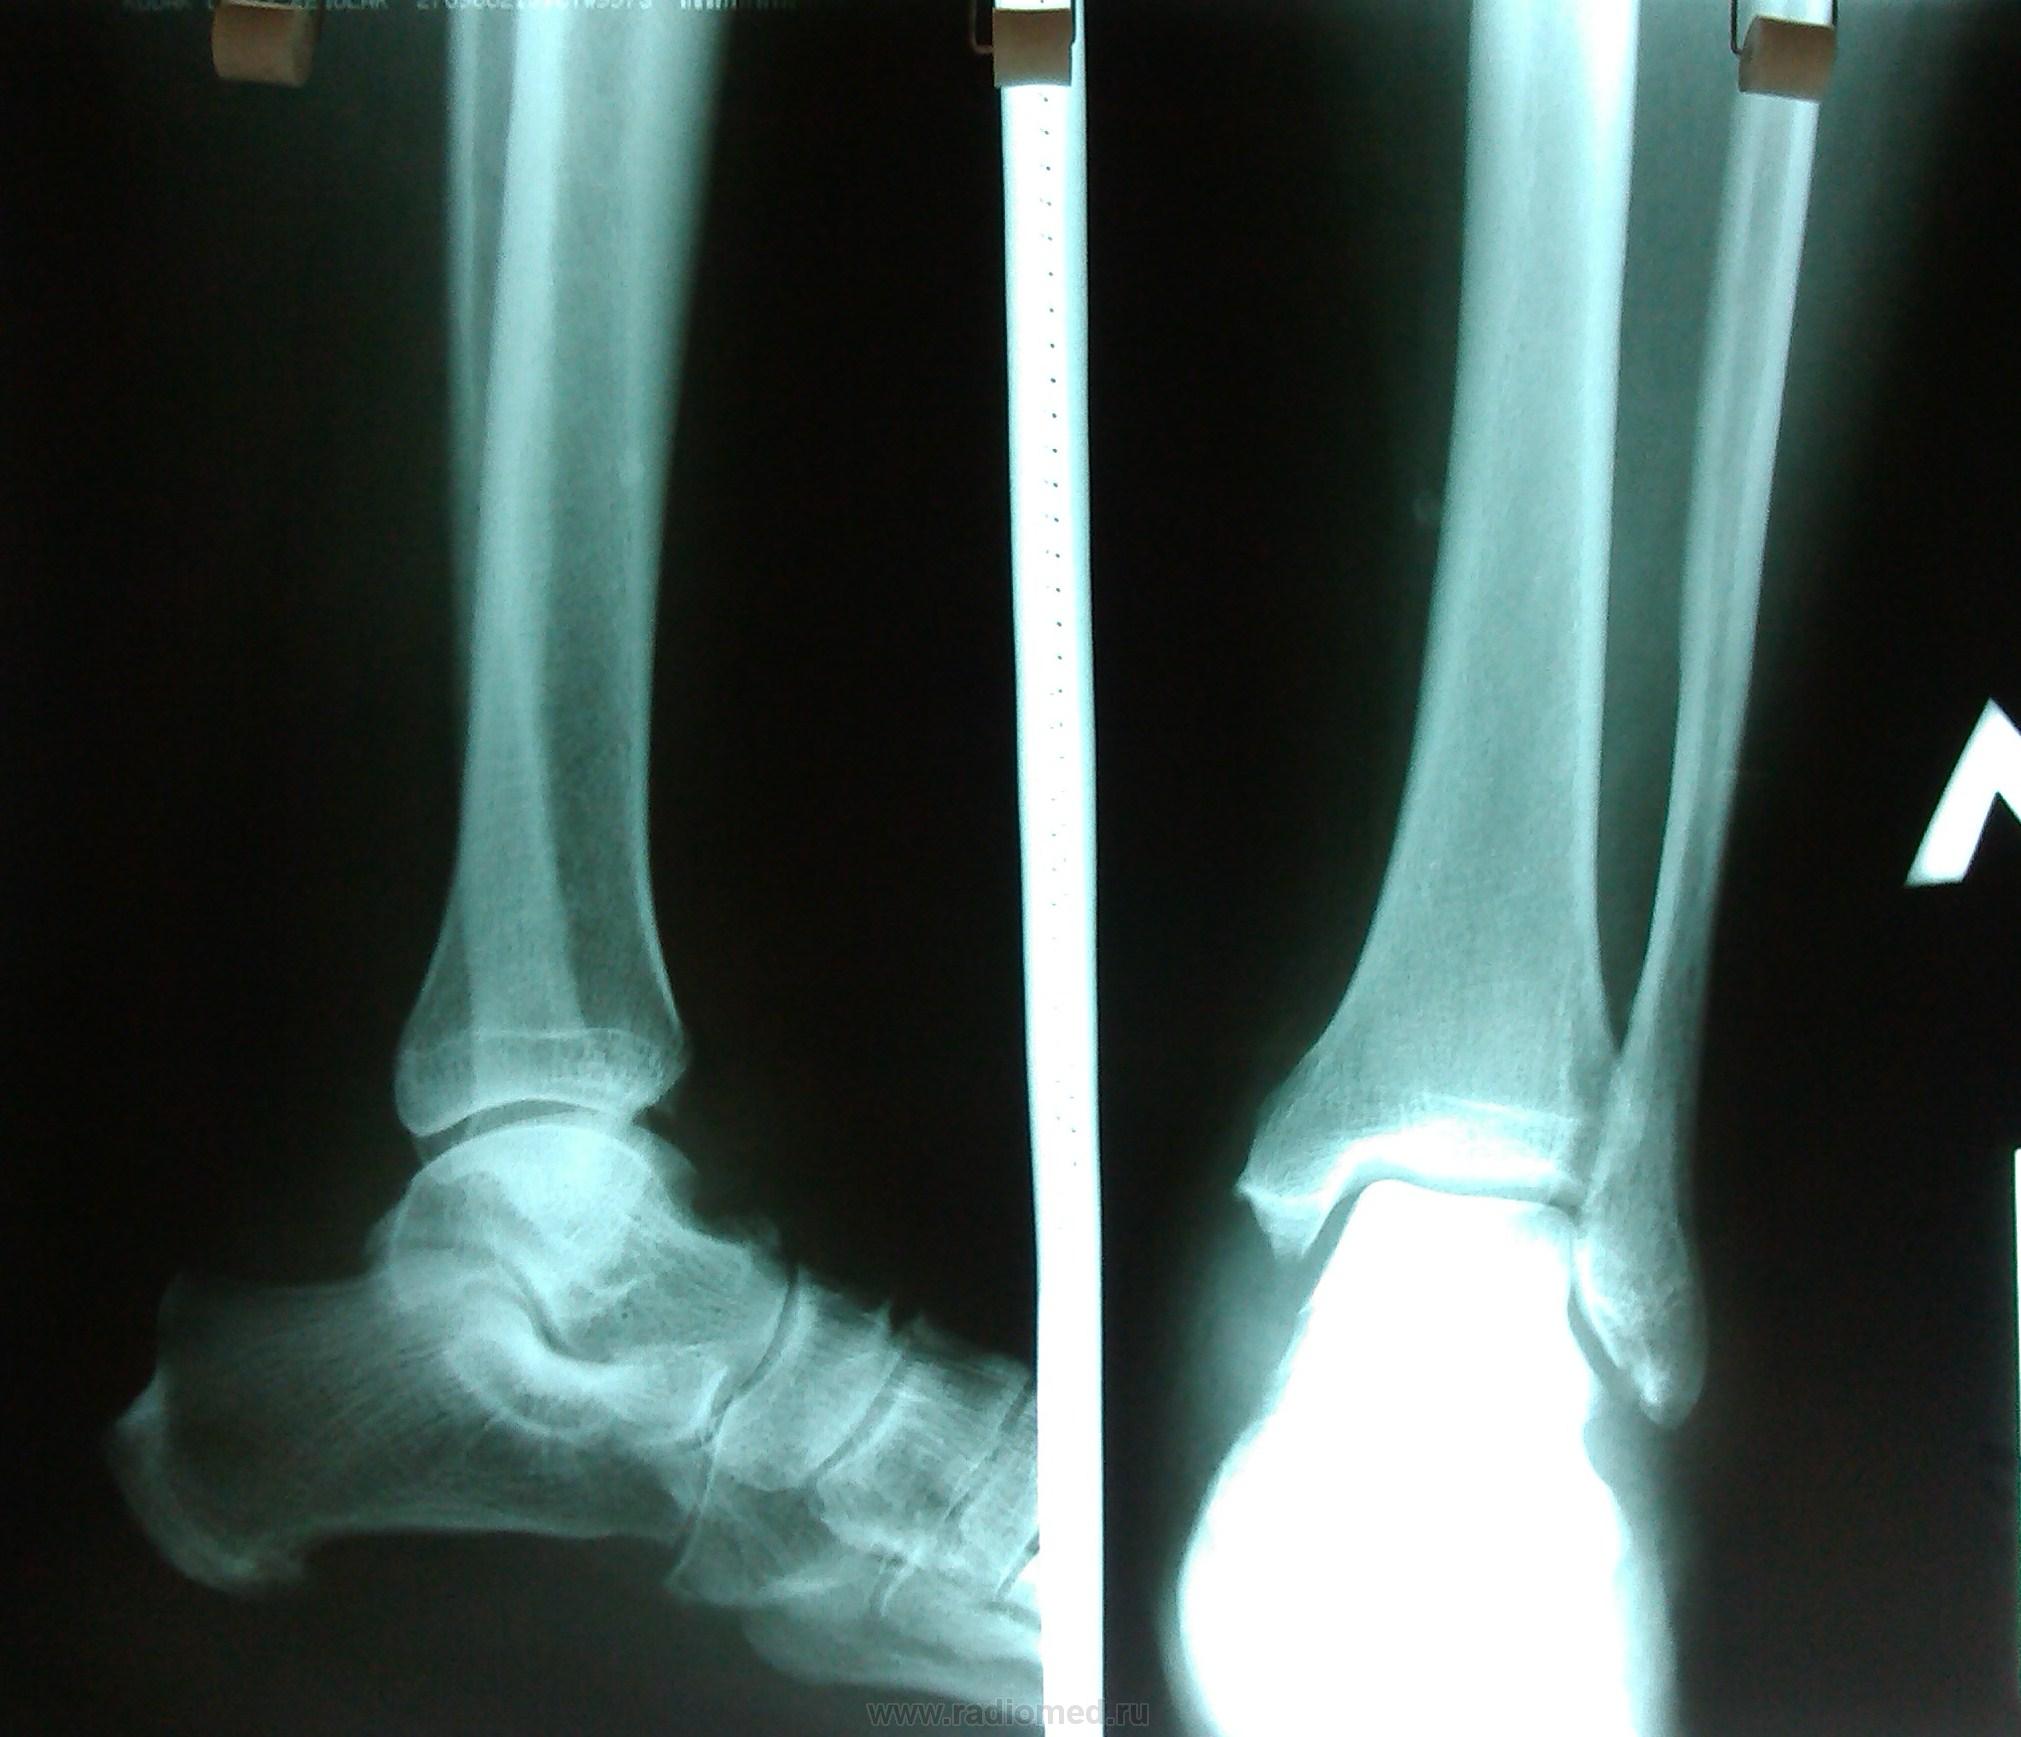

Пол пациента: Женский пол Тип патологии: Другое Область исследования: Скелетно-мышечная система Методы исследования: Rg Пациентка , 49 лет. Ds: Остеоартроз обоих голеност-х суставов. Дополнительная тень левой большеберцовой кости? https://radiomed.ru/sites/default/files/styles/case_slider_image/public/user/18609/img_20130813_160611.jpg?itok=MJd9oCoL ID:30750 Втр, 13/08/2013 - 22:20 #1 Андрей Юрьевич Не на сайте Был на сайте: 6 дней 20 часов назад Зарегистрирован: 16.11.2008 - 22:16 Публикации: 18098 Сосуд, по всей видимости. Андрей Юрьевич Ср, 14/08/2013 - 11:56 #2 Алексей Игореви... Не на сайте Был на сайте: 6 лет 10 месяцев назад Зарегистрирован: 08.08.2012 - 21:52 Публикации: 786 Ну так она не в кости. Или сосуд, или какой-то кальцинат в мягких тканях. "Обучая других - учишься сам". Н.И.Пирогов Ср, 14/08/2013 - 12:40 #3 stovbav Не на сайте Был на сайте: 2 года 2 месяцев назад Зарегистрирован: 20.12.2009 - 17:28 Публикации: 7066 Гетеротопическое окостенение в параоссальных тканях. Генез - как правило постравматического характера, но не факт. Болезни ног: виды, симптомы, причины, профилактика и лечение

Сосуд, по всей видимости.

Ну так она не в кости. Или сосуд, или какой-то кальцинат в мягких тканях.

Гетеротопическое окостенение в параоссальных тканях.

Генез - как правило постравматического характера, но не факт.